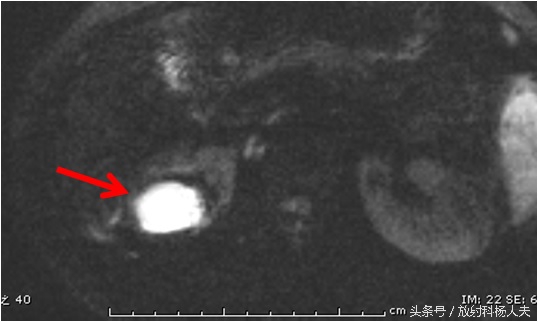

这个囊性病变到底是什么?囊性肿瘤?有无办法继续明确呢?有!那就是MRI,除了进一步明确,还能更清楚的显示窦道的走行。下图这个序列,叫DWI,红箭所示的白白的东西,证明这是一个脓肿!

终于搞清楚了,原来一个月前的腰痛,是肾脏的脓肿,而且MRI上还能清晰的显示脓肿破口的位置,下图中黄箭所示(红箭为脓肿)。